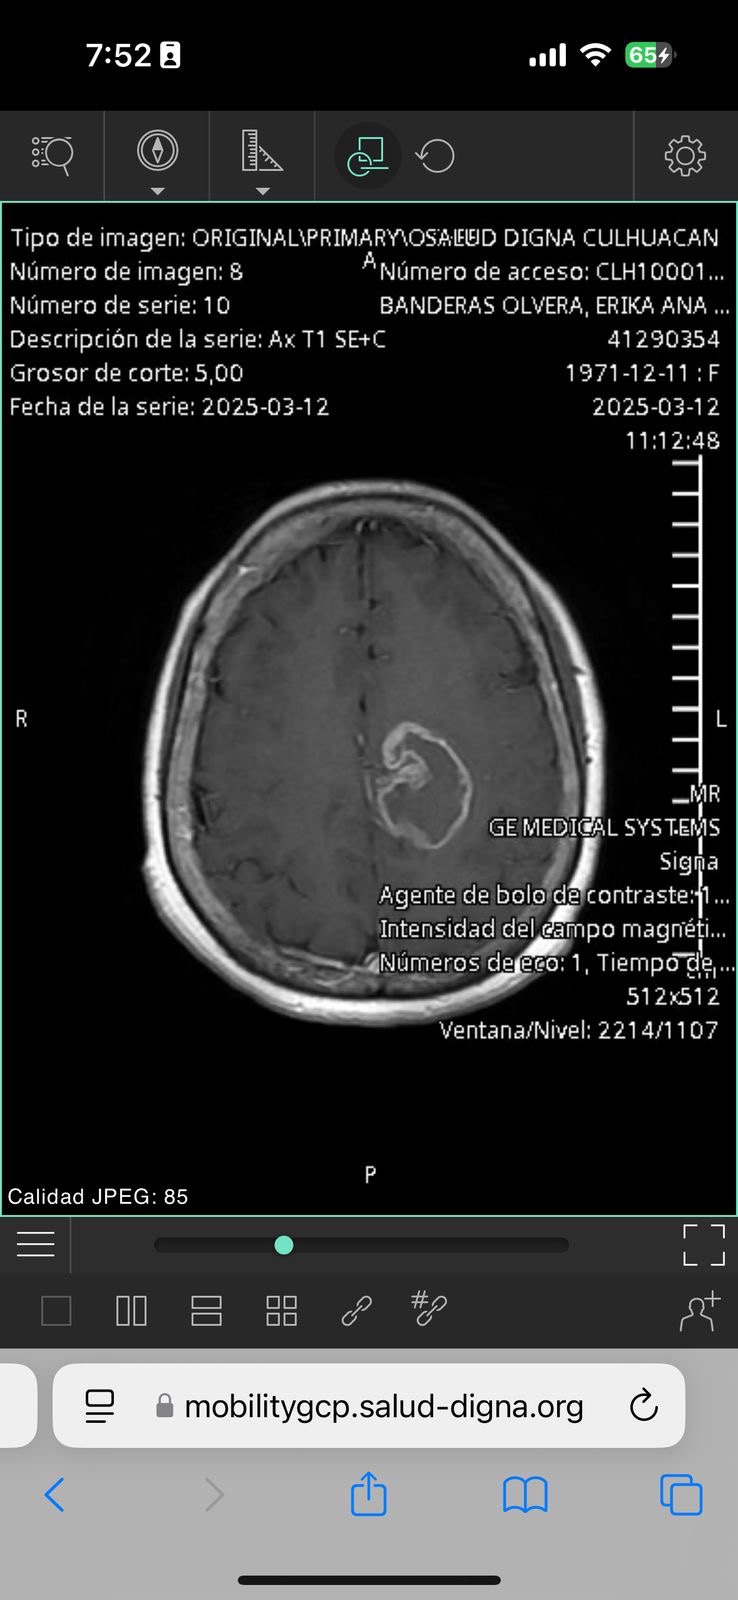

Mi mamá es una mujer fuerte, valiente y llena de vida. También mi mejor amiga. Hace poco nos dieron una noticia que partió nuestra vida en dos: le diagnosticaron glioblastoma multiforme, un tumor cerebral agresivo que afectó el lado izquierdo de su cerebro. Desde entonces, nuestra vida se ha convertido en una batalla diaria por su salud.

My mom is a strong, brave, and full of life woman and also my best friend. Not long ago, we received news that changed our lives forever: she was diagnosed with glioblastoma multiforme, an aggressive brain tumor that affected the left side of her brain. Since then, our lives have become a daily battle for her health.